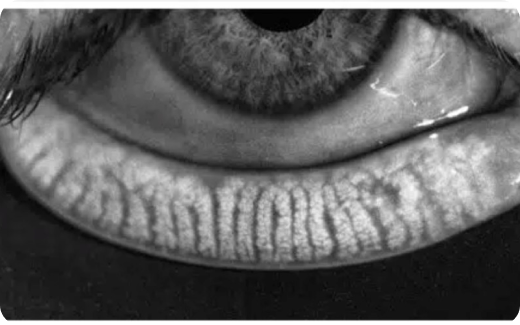

Dry eye, MGD, Rosacea, Acne, skin tightening, age spots, dilated blood vessels